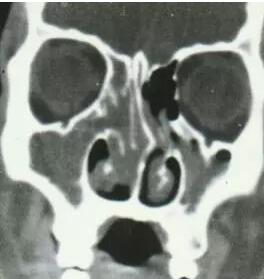

鼻中隔偏曲

高位弯曲压迫中鼻甲

同侧中鼻道、嗅沟引流障碍

阻塞性鼻窦炎

对侧中、下鼻甲增生